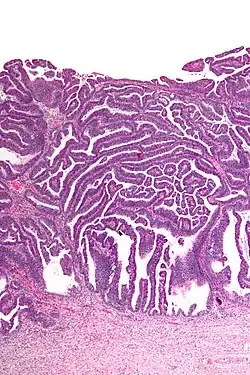

Micrograph of a villoglandular adenocarcinoma the cervix. H&E stain.

The name of the lesion describes it microscopic appearance. It has nipple-like structures with fibrovascular cores (papillae) that are long in relation to their width (villus-like), which are covered with a glandular pseudostratified columnar epithelium.